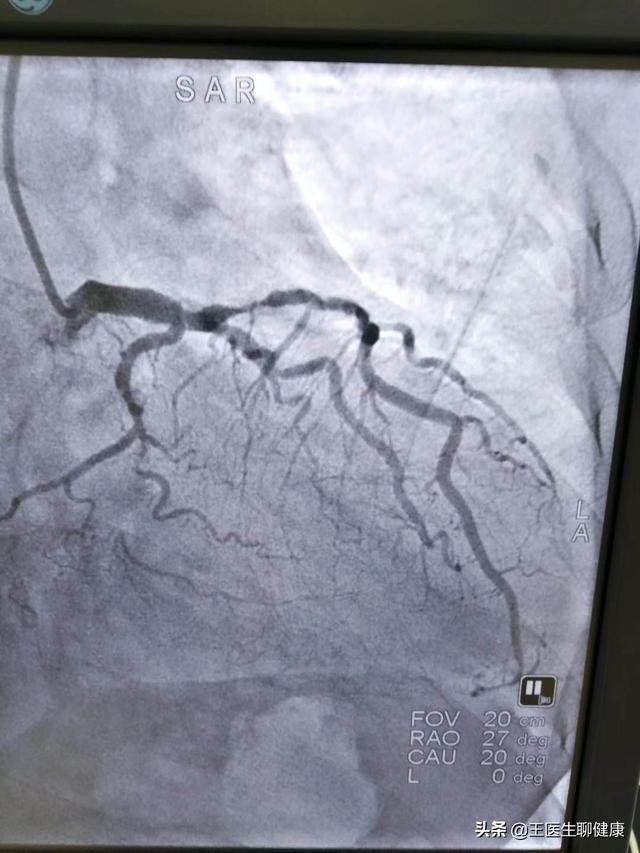

下図は左主幹部の多枝病変である。